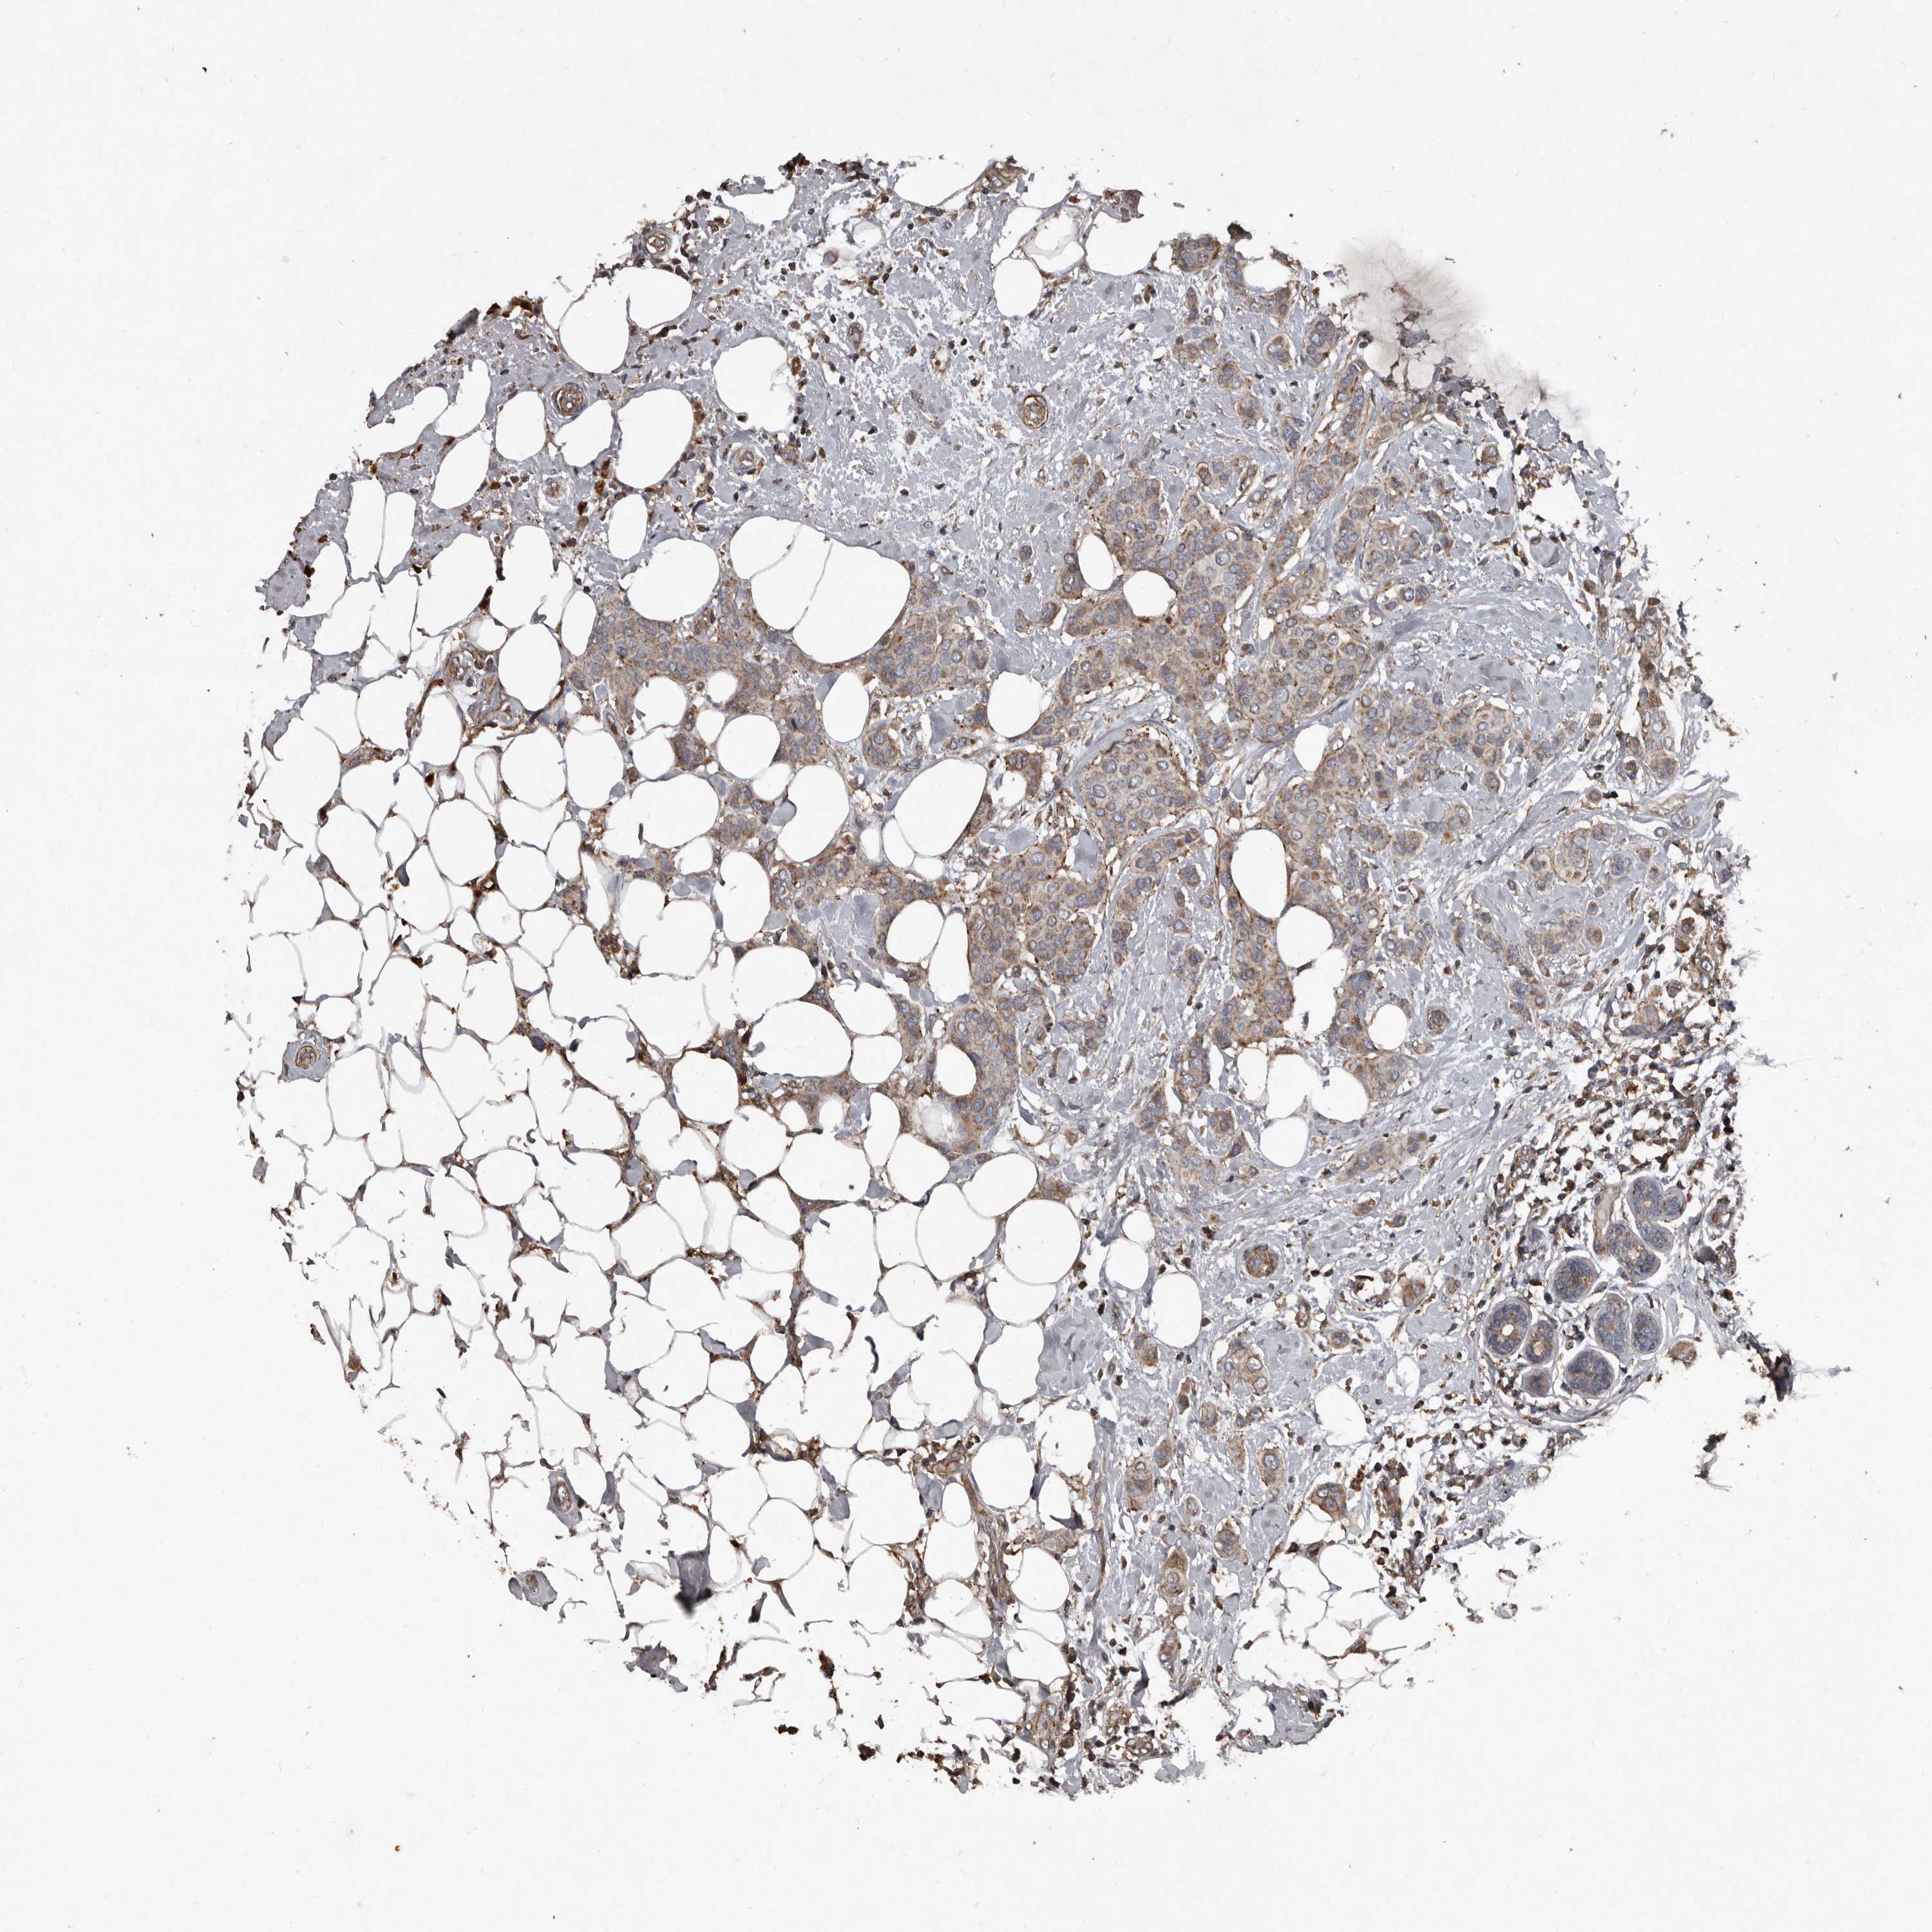

CANCER BREAST CANCER Show tissue menu

BRCA TCGA BRCA VALIDATION PROTEIN EXPRESSION